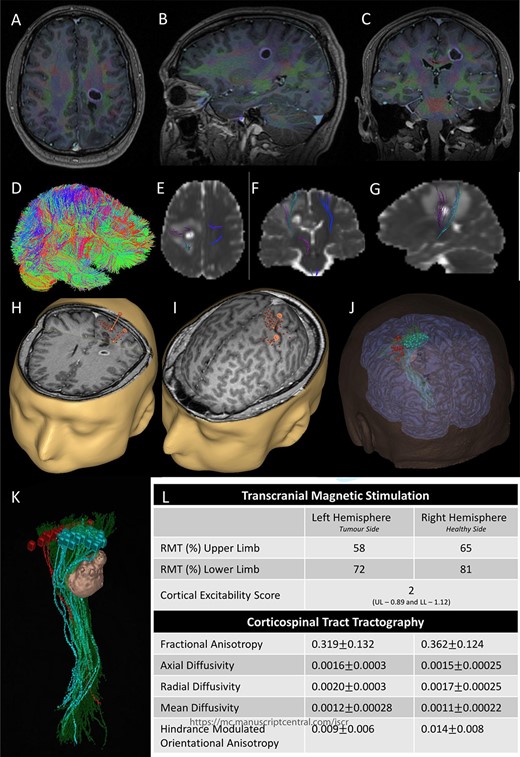

Preoperative imaging; (A–C) axial, sagittal and coronal T1-wieghted magnetic resonance imaging (MRI) images, with gadolinium demonstrating a contrast enhancing lesion in the left corona radiata.

A 42-year-old, right-handed gentleman presented with 1-month history of right foot weakness and focal seizures. Imaging revealed a 1.6 × 1.4 × 1.6 cm enhancing lesion in the left corona radiate (Fig. 1). He underwent stereotactic frameless needle biopsy using the method previously described by our group [6]. The biopsy result was inconclusive, the procedure was uneventful and he recovered without neurological deficit. Post-operative computed tomography (CT) showed the biopsy site was posterolateral to the lesion and following discussion in our neuro-oncology multidisciplinary team meeting the consensus was to perform an open biopsy.